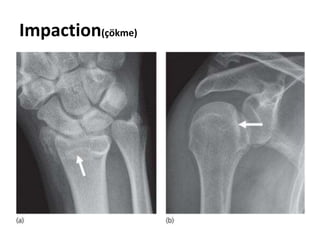

Impaction(çökme)

• 3.